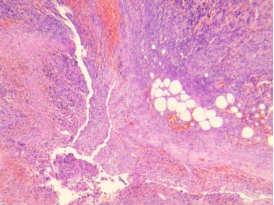

化脓性阑尾炎

阑尾表面有灰白色脓性渗出物,腔内充满中性粒细胞,各层有大量中性粒细胞浸润及充血水肿。

管壁全层大量中性粒细胞浸润